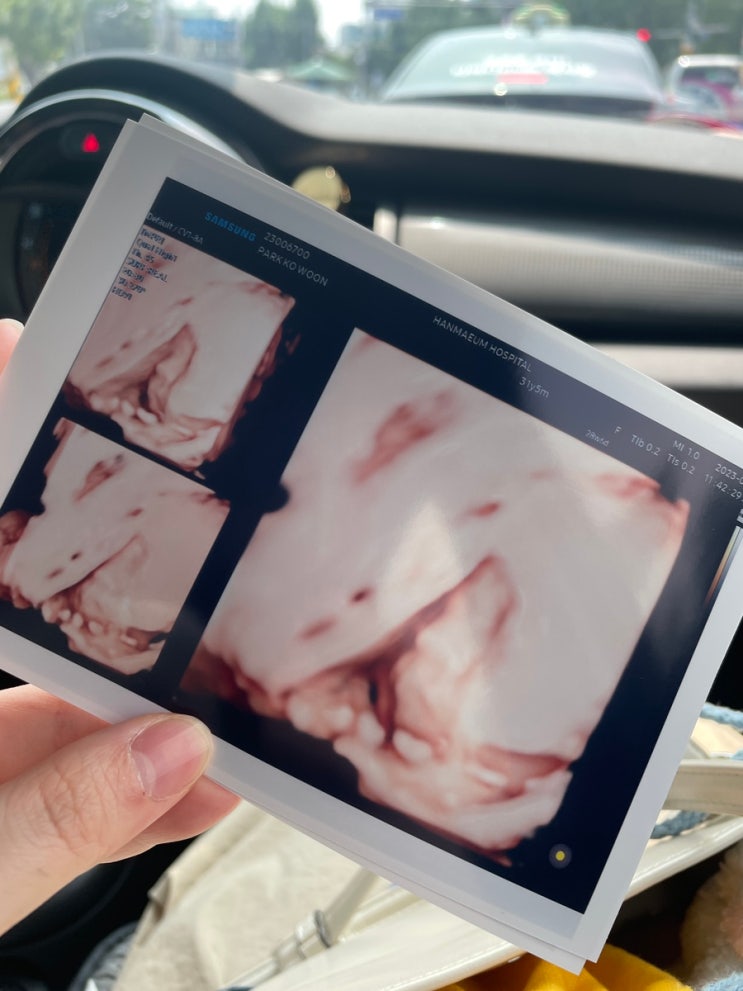

[임신 8개월차 28W6D] 코로나 이후 검진 (입체초음파 실패, 양수량 적음, 소양증 재발..)

한마음병원에서 진행한 1,2차 기형아 검사(목요일 오후)는 그 다음주 월요일에 정상이라고 문자가 왔었다 ...